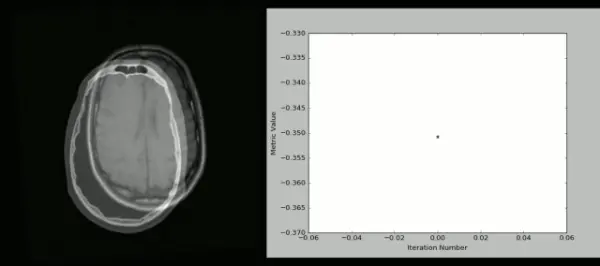

下面就是用SimpleITK和Python创建的可视化的CT/MR图: